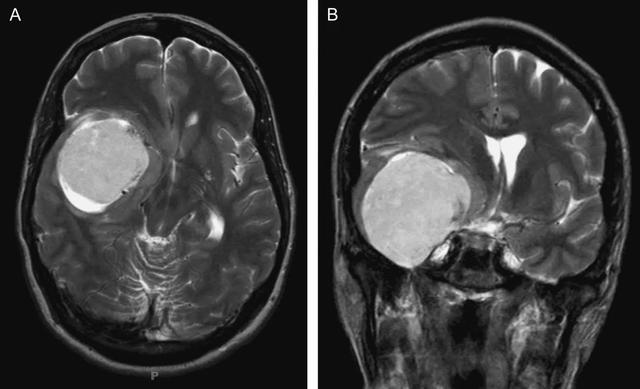

患者M(jìn)R檢查結(jié)果顯示其右側(cè)橋小腦角區(qū)有占位;頭部CTA顯示占位區(qū)附近有大部分鈣化。較終,李阿姨被診斷為右側(cè)橋小腦角區(qū)腦膜瘤。

隨后,經(jīng)過INC國際神經(jīng)外科醫(yī)生集團(tuán)的協(xié)調(diào),李阿姨及其女兒前往德國接受巴特朗菲教授的治療。巴特朗菲教授為患者行右側(cè)橋小腦角區(qū)腦膜瘤切除術(shù),將一顆像橡膠一樣堅(jiān)硬、番茄般大小的瘤子從患者腦中完全切除了。

橋小腦角區(qū)腦膜瘤是指位于腦內(nèi)巖骨后表面和附近的硬腦膜,包括起源于巖骨后或侵及小腦幕的腦膜瘤。此類腦膜瘤的質(zhì)地通常會比較堅(jiān)硬。